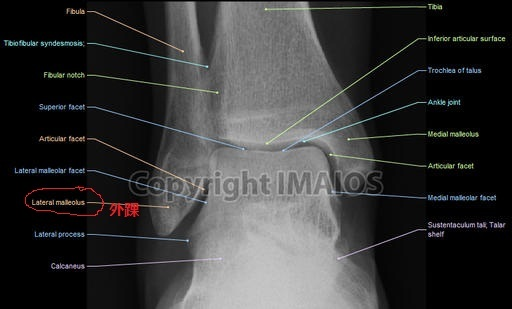

腓骨外踝

外踝骨折图

外踝骨折

(答案:①腓骨头 ②腓骨颈 ③胫骨髁间隆起 ④胫骨粗隆 ⑤外踝 ⑥内踝)